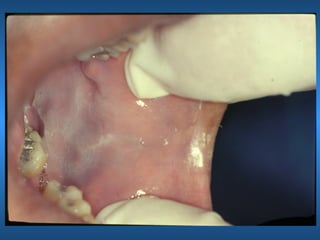

Leucoedema

• Etiologia

• Características Clínicas

• Raça

• Manobra Clínica

• Aspectos Histológicos